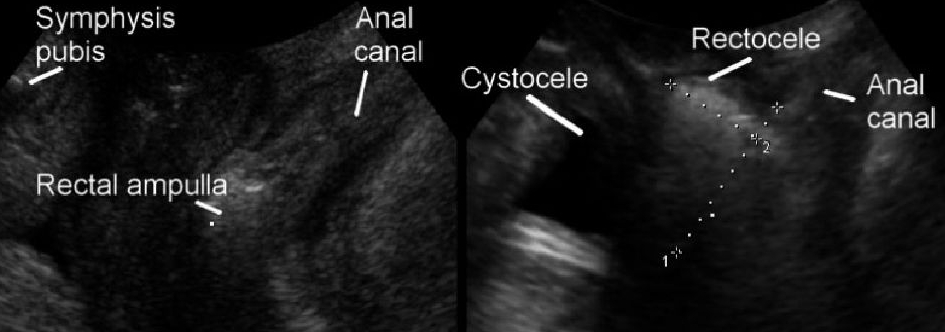

2.子宫脱垂。目前超声对子宫脱垂分度尚无统一定论。

3.直肠膨出:又称为阴道后壁膨出,亦称为直肠阴道膨出或者直肠阴道疝。该膨出物与肛管约呈90度夹角。